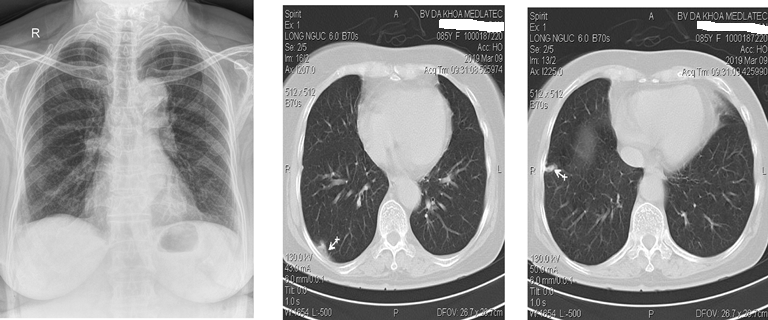

Lực lượng Đặc nhiệm Dịch vụ Dự phòng Hoa Kỳ khuyến nghị sàng lọc phổi hàng năm bằng CT ngực liều thấp (LDCT) cho những người từ 50 đến 80 tuổi có nguy cơ mắc ung thư phổi cao, chẳng hạn như những người hút thuốc lâu năm. Cùng với hình ảnh của phổi, các bản quét cũng cung cấp thông tin về các cấu trúc khác trong ngực.

Xu và các đồng nghiệp trước đây đã phát triển, thử nghiệm và phát hành công khai một thuật toán AI tự động lấy các phép đo thành phần cơ thể từ LDCT sàng lọc phổi. Thành phần cơ thể là thước đo tỷ lệ mỡ, cơ và xương trong cơ thể. Thành phần cơ thể bất thường, chẳng hạn như béo phì và mất khối lượng cơ, có liên quan đến các tình trạng sức khỏe mãn tính như rối loạn chuyển hóa. Các nghiên cứu cũng chỉ ra rằng thành phần cơ thể rất hữu ích trong việc phân tầng nguy cơ và tiên lượng bệnh tim mạch và bệnh phổi tắc nghẽn mạn tính. Trong điều trị ung thư phổi, thành phần cơ thể đã được chứng minh là có ảnh hưởng đến khả năng sống sót và chất lượng cuộc sống.

Đối với nghiên cứu mới, nhà nghiên cứu đã đánh giá giá trị gia tăng của các phép đo thành phần cơ thể có nguồn gốc từ AI. Họ đã sử dụng ảnh chụp CT của hơn 20.000 cá nhân được rút ra từ Thử nghiệm sàng lọc phổi quốc gia.

Kết quả cho thấy việc bao gồm các phép đo này đã cải thiện dự đoán rủi ro tử vong do ung thư phổi, bệnh tim mạch và tử vong do mọi nguyên nhân.